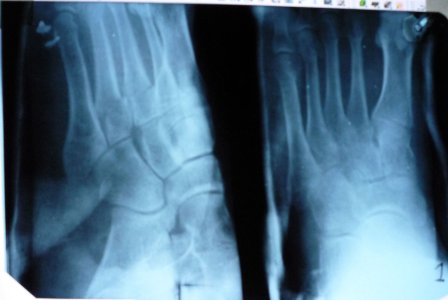

Здравствуйте, 16.10.09 в пятницу вечером на тренировке разворачиваясь на одной ноге сломал 3 и 4 плюсневые кости ,в травмопункте сделали снимки, после чего дежурный врач накладывая гипс попытался вправить смещеные плюсневые кости, но у него ничего не вышло, что видно на повторном снимке .Посоветовал с понедельника обратится в больницу по месту жительства и возможно готовится к операции.... Посмотрите пожалуйста можно ли вправить на место кости без операционного вмешательства и каковы шансы на их успешное ПРАВИЛЬНОЕ сростание.